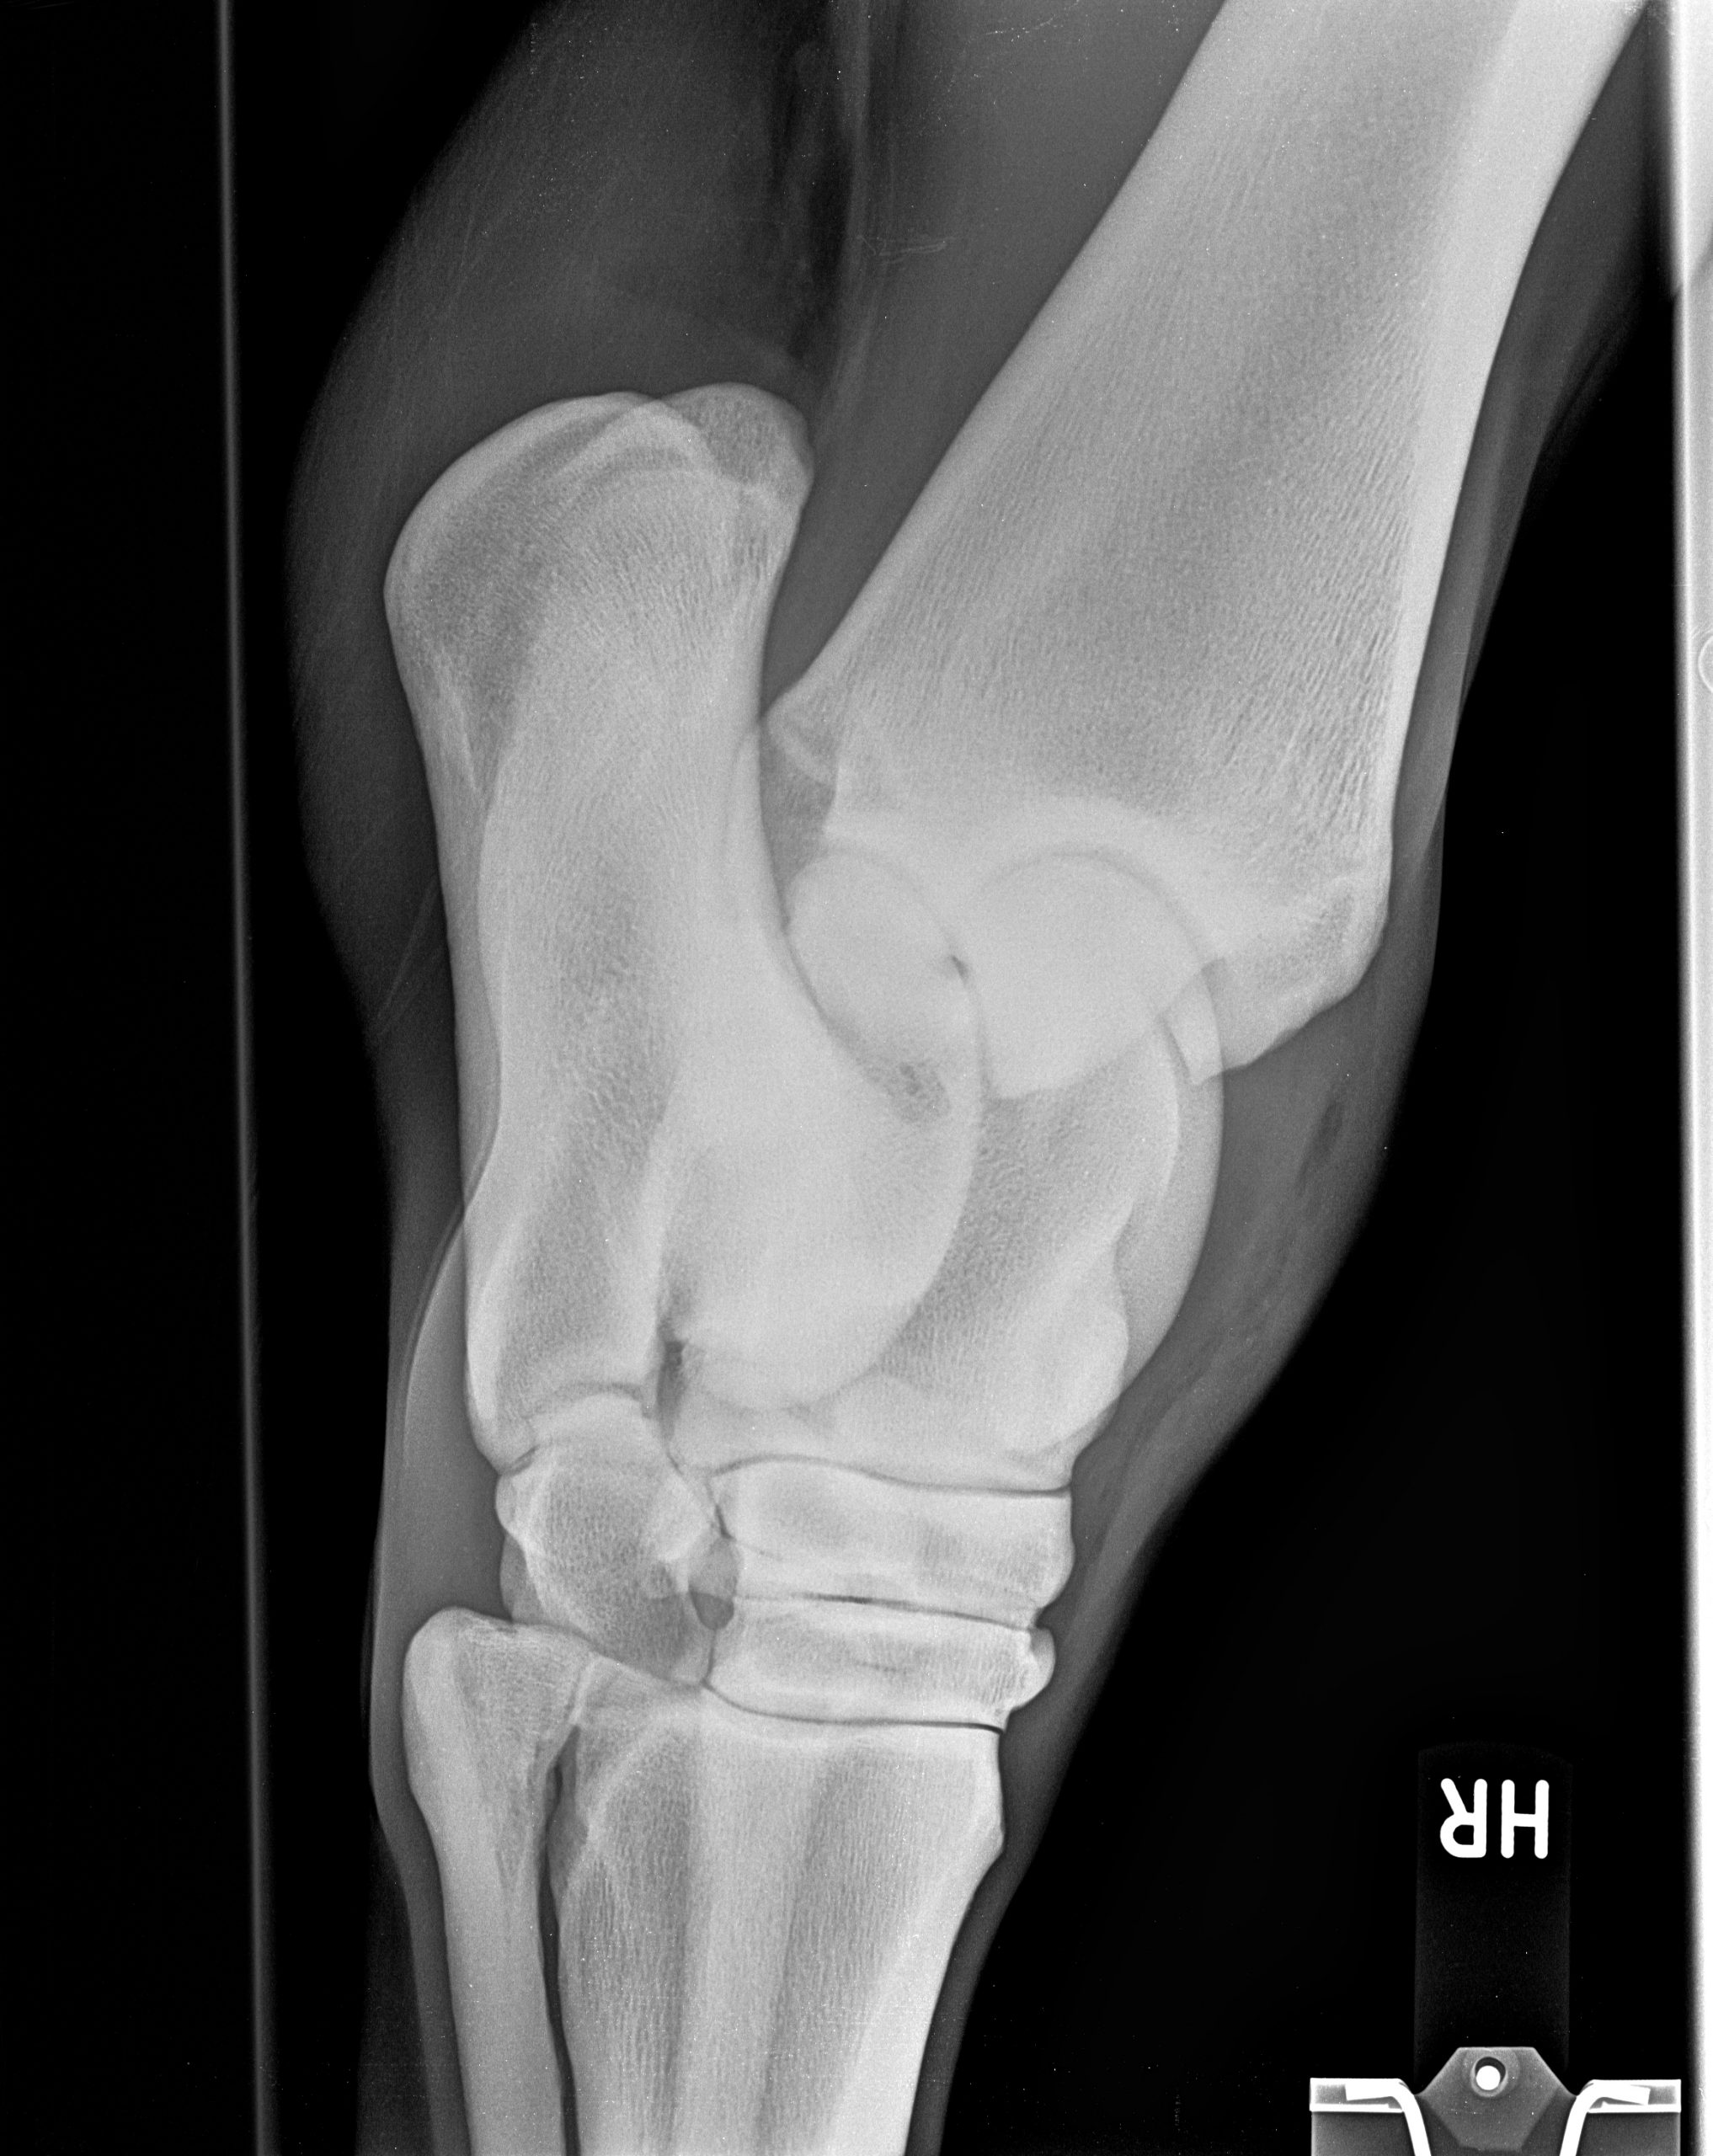

Röntgenbilder

Diese Sammlung zeigt verschiedene Röntgenaufnahmen, die eine Vielzahl von anatomischen Strukturen und potenziellen Gesundheitszuständen veranschaulichen. Jede Aufnahme bietet wertvolle Einblicke in die Gesundheit und das Wohlbefinden Ihrer Pferde.